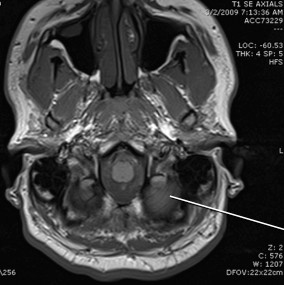

tegmentum of the pons

basis of the pons

crus cereberi